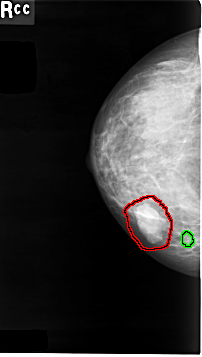

C_0008_1.RIGHT_CC

RIGHT_CC LINES 4640 PIXELS_PER_LINE 2624 BITS_PER_PIXEL 12 RESOLUTION 50 OVERLAY

FILE: C_0008_1.RIGHT_CC.OVERLAY

TOTAL_ABNORMALITIES 2

ABNORMALITY 1

LESION_TYPE MASS SHAPE LOBULATED MARGINS MICROLOBULATED

ASSESSMENT 4

SUBTLETY 5

PATHOLOGY MALIGNANT

TOTAL_OUTLINES 1

BOUNDARY

ABNORMALITY 2

LESION_TYPE CALCIFICATION TYPE PUNCTATE DISTRIBUTION CLUSTERED

PATHOLOGY BENIGN